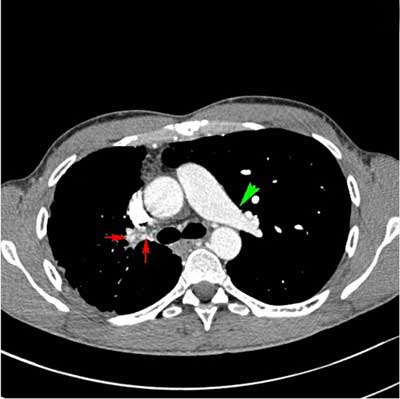

Figure 3

CECT of the thorax, soft tissue window, axial image. Normal appearance of the left pulmonary artery (green arrow). Absent right pulmonary artery. Prominent bronchial arteries supplying the right lung (red arrows). Smaller volume of the right lung.